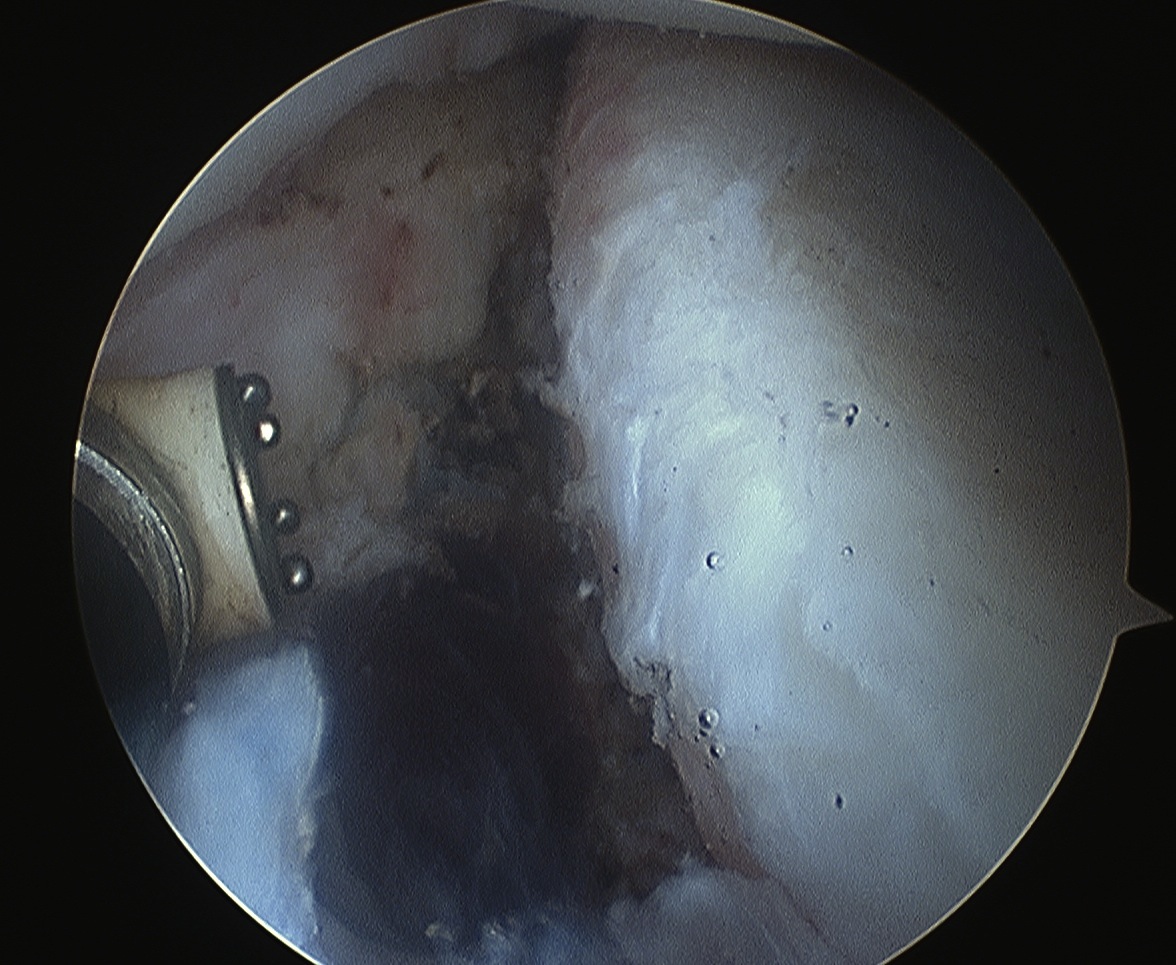

Pass sutures and tie knots

Typically curved suture passers

Aim to tighten capsule medially and superiorly onto glenoid

Shoulder Bankart Repair Suture PasserShoulder Instability inferior Suture passage

Arthroscopy Anterior Bankart RepairShoulder Bankart RepairShoulder Scope Bankart Repair 2

Bankart repairBankart